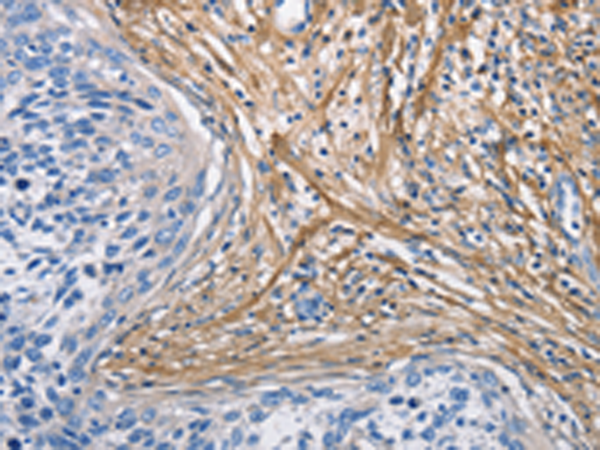

分类: 科研抗体货号: P07217别名: EB1; SCAF1; SCAFI; SIG81; COX7AR; COX7RP应用: WB,IHC反应种属: Human, Mouse

分类: 科研抗体货号: P07218别名: COX11P应用: WB,IHC反应种属: Human, Mouse

分类: 科研抗体货号: P07216别名: NOC4, COX4NB, C16orf2, C16orf4, FAM158B应用: WB,IHC反应种属: Human, Mouse, Rat

分类: 科研抗体货号: P07243别名: DCIR; LLIR; CD367; DDB27; CLECSF6; HDCGC13P应用: WB,IHC反应种属: Human

分类: 科研抗体货号: P07239别名: HLP; CP33; CP34; CYP3A; NF-25; CYP3A3; P450C3; CYPIIIA3; CYPIIIA4; P450PCN1应用: WB,IHC反应种属: Human

分类: 科研抗体货号: P07212别名: AOM; ANFH; SEDC; STL1; COL11A3应用: WB,IHC反应种属: Human, Mouse, Rat

分类: 科研抗体货号: P07237别名: AHH, AHRR, CP11, CYP1, P1-450, P450-C, P450DX应用: WB,IHC反应种属: Human, Mouse, Rat